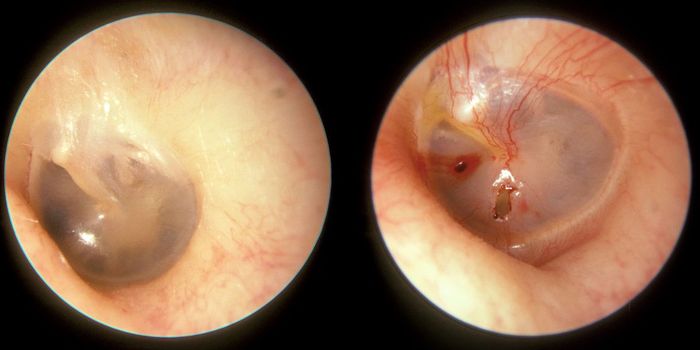

APR 01, 2015Chemistry & PhysicsPhysicists have shed light on the intricate dynamics underpinning a mysterious tongue condition that has been puzzling t ...